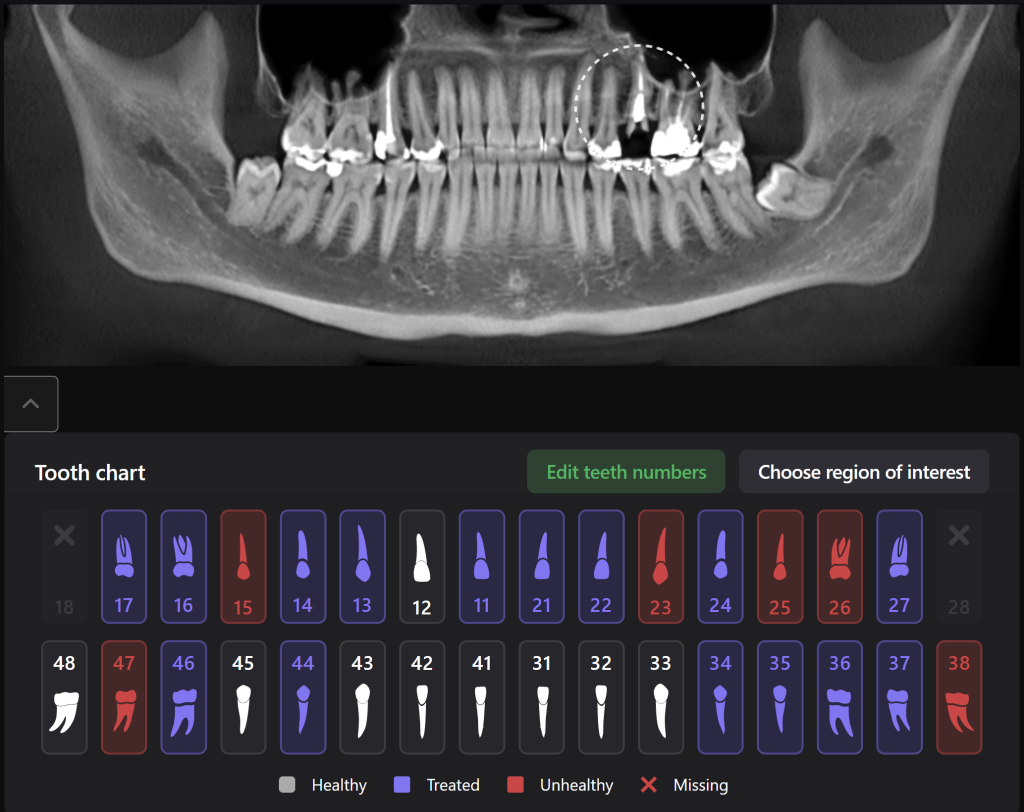

The planning of immediate implant placement using Diagnocat AI has many advantages for both the doctor and the patient. Let’s consider them using a clinical case example, in which the removal of tooth 25 (Universal 13) and subsequent implant placement were planned

The patient came with complaints that his dental crown on tooth 25 (Universal 13) fell out

In order to predict the prognosis of the tooth, data from the Diagnocat radiological report and visualization capabilities of the 3D-Viewer tool were utilized, in addition to a clinical examination